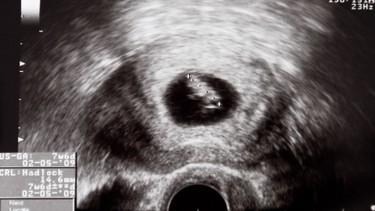

Trong suốt thai kỳ, sức khỏe của mẹ và sự phát triển của thai nhi là mối quan tâm hàng đầu. Do đó, khi có chỉ định chụp X quang nhiều phụ nữ mang thai không khỏi hoang mang vì lo sợ ảnh hưởng của tia X đến thai nhi. Việc hiểu đúng về quy trình chẩn đoán hình ảnh này sẽ giúp mẹ bầu chủ động bảo vệ thai kỳ của mình.

Một trong những thắc mắc phổ biến của các mẹ bầu khi cần chẩn đoán hình ảnh đó là “Bầu có chụp X quang được không?”. Thực tế, việc chụp X quang trong thai kỳ không bị cấm tuyệt đối nhưng cần được cân nhắc kỹ lưỡng để đảm bảo an toàn cho thai nhi.

Theo các chuyên gia, nguy cơ tổn hại đến thai nhi do tia X là tương đối thấp, đặc biệt nếu chỉ thực hiện chụp ở các vùng không gần bụng như tay, chân, đầu hoặc ngực. Trong trường hợp khẩn cấp hoặc khi lợi ích chẩn đoán vượt trội, chụp X‑quang vẫn được chỉ định. Tuy nhiên, nếu thai phụ tiếp xúc với liều phóng xạ lớn hơn khoảng 50 mGy (5 rad) ở bụng/chậu, đặc biệt trong 3 tháng đầu, rủi ro có thể tăng.